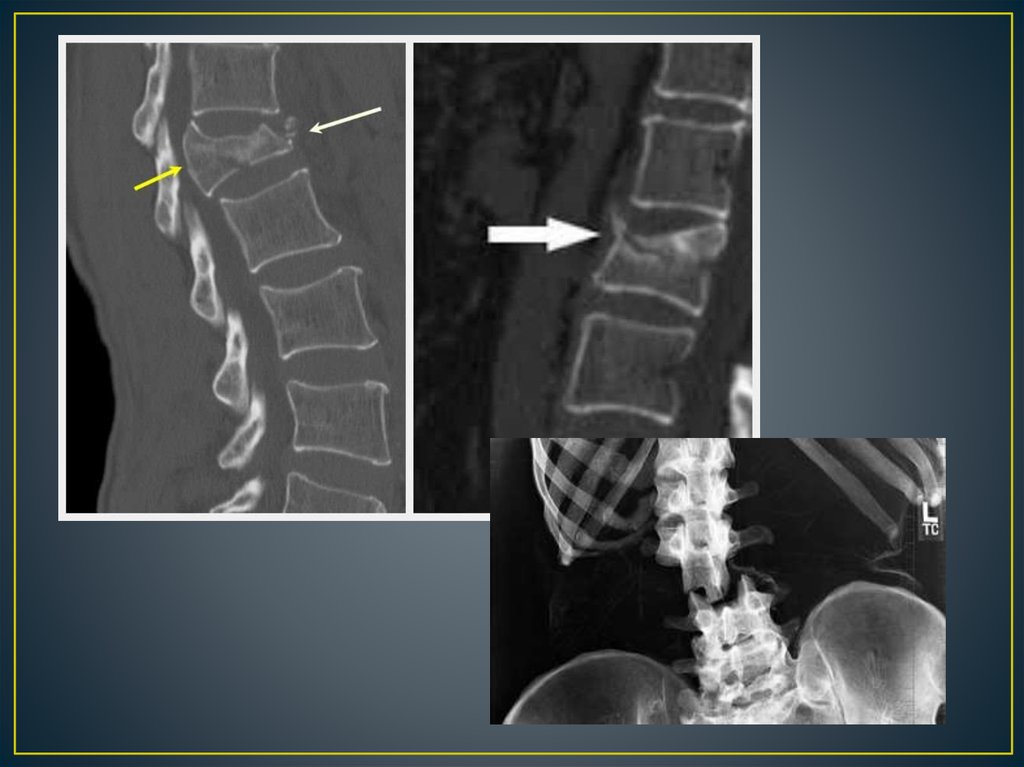

Позвоночно – спинальная травма